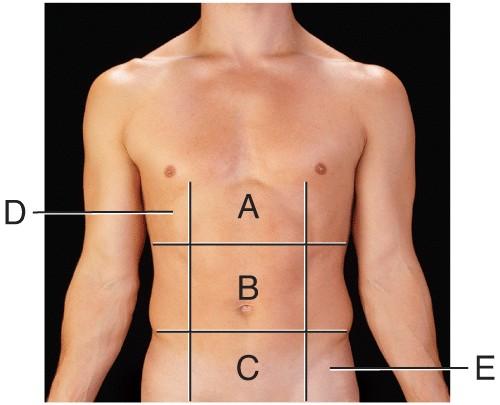

Name the region B.

middle hypochondriac

hypogastric

epigastric

Umbilical

Umbilical

Name the region A.

epigastric

umbilical

right hypochondriac

hypogastric

epigastric

Name the region E.

left hypochondriac

right lumbar

epigastric

left iliac

left iliac

Name the region C.

middle iliac

epigastric

umbilical

hypogastric

hypogastric

Name the region D.

Right Hypochondriac

Left Hypochondriac

epigastric

Right Lumbar

Right Hypochondriac

The liver is found in the region labeled:

A